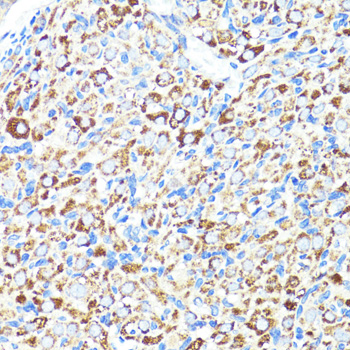

| Application: | WB IHC |

| Application: | WB IHC |

| Recommended Dilution: | WB 1:500 - 1:2000 IHC 1:50 - 1:100 |